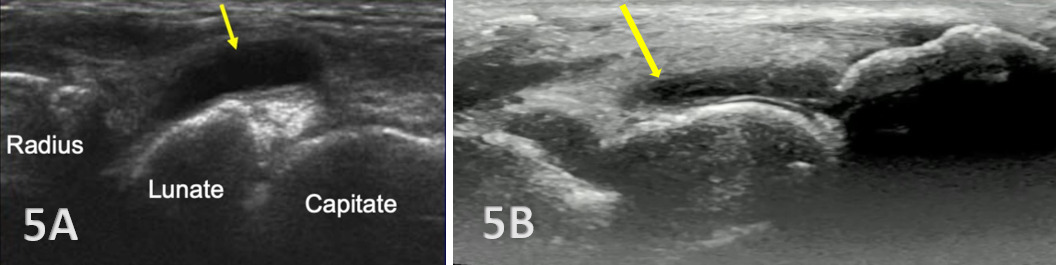

Normal Sonographic Appearance

Typically, the radiocarpal joint is viewed in both the LAX and SAX. Typically, there is no joint effusion; therefore, the joint recess is collapsed or barely visible on ultrasound. The capsule should be thin and not distended. The dorsal ligaments are normally continuous and should exhibit a normal fibrillar pattern, indicating they are intact and healthy. The synovium is typically visualized as a very thin echogenic line, with no synovial hypertrophy. The articular surfaces of the radius and the carpal bones should include uniform anechoic or hypoechoic cartilage layers and demonstrate smooth, continuous hyperechoic cortical lines with no physical breaks or breaches.

Pathologic Findings in Injured Radiocarpal Joints

Hyperechoic irregularities of bone of the radius, scaphoid, and lunate are visible.

Hypoechoic bands of synovial tissue folds are present.

Anechoic or hypoechoic joint effusion and/or synovitis (synovial hypertrophy) and cysts within the joint.

Joint effusion is somewhat compressible and mobile when transducer pressure is applied to the area. This is different from synovitis, which appears as hypoechoic or isoechoic, non-compressible tissue within the joint recess. Synovitis may be associated with conditions such as rheumatoid arthritis, psoriatic arthritis, or other inflammatory arthropathies. Lastly, a ganglion cyst may appear as a well-defined, round or lobulated cystic structure with anechoic or hypoechoic internal contents. The cyst will usually have a small, smooth wall and exhibit posterior acoustic enhancement. These cysts will typically be minimally or non-compressible and painful.